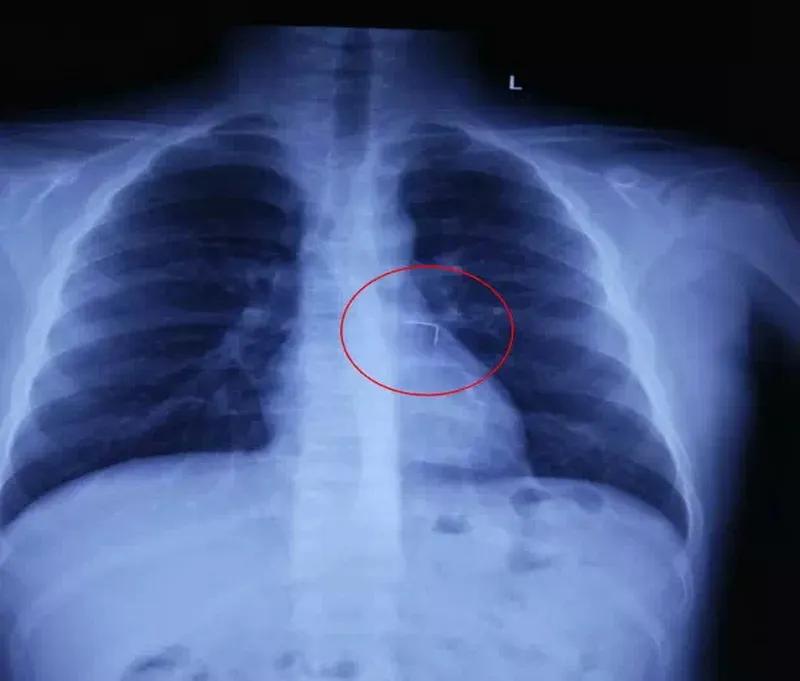

“支气管异物”具体有哪些症状呢? 支气管异物可不是小事!急性期异物刚呛进去,会